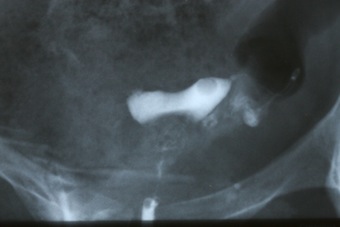

1) ГСГ - из-за спазма на фоне нервных переживаний (скорее всего) контрастная жидкость протекла только в одну трубу, и то еле-еле, вторая вообще осталась нетронутой (судя по снимку), а в нижней части матки какой-то "дефект" - контраст не пробил его, осталось темное пятно..